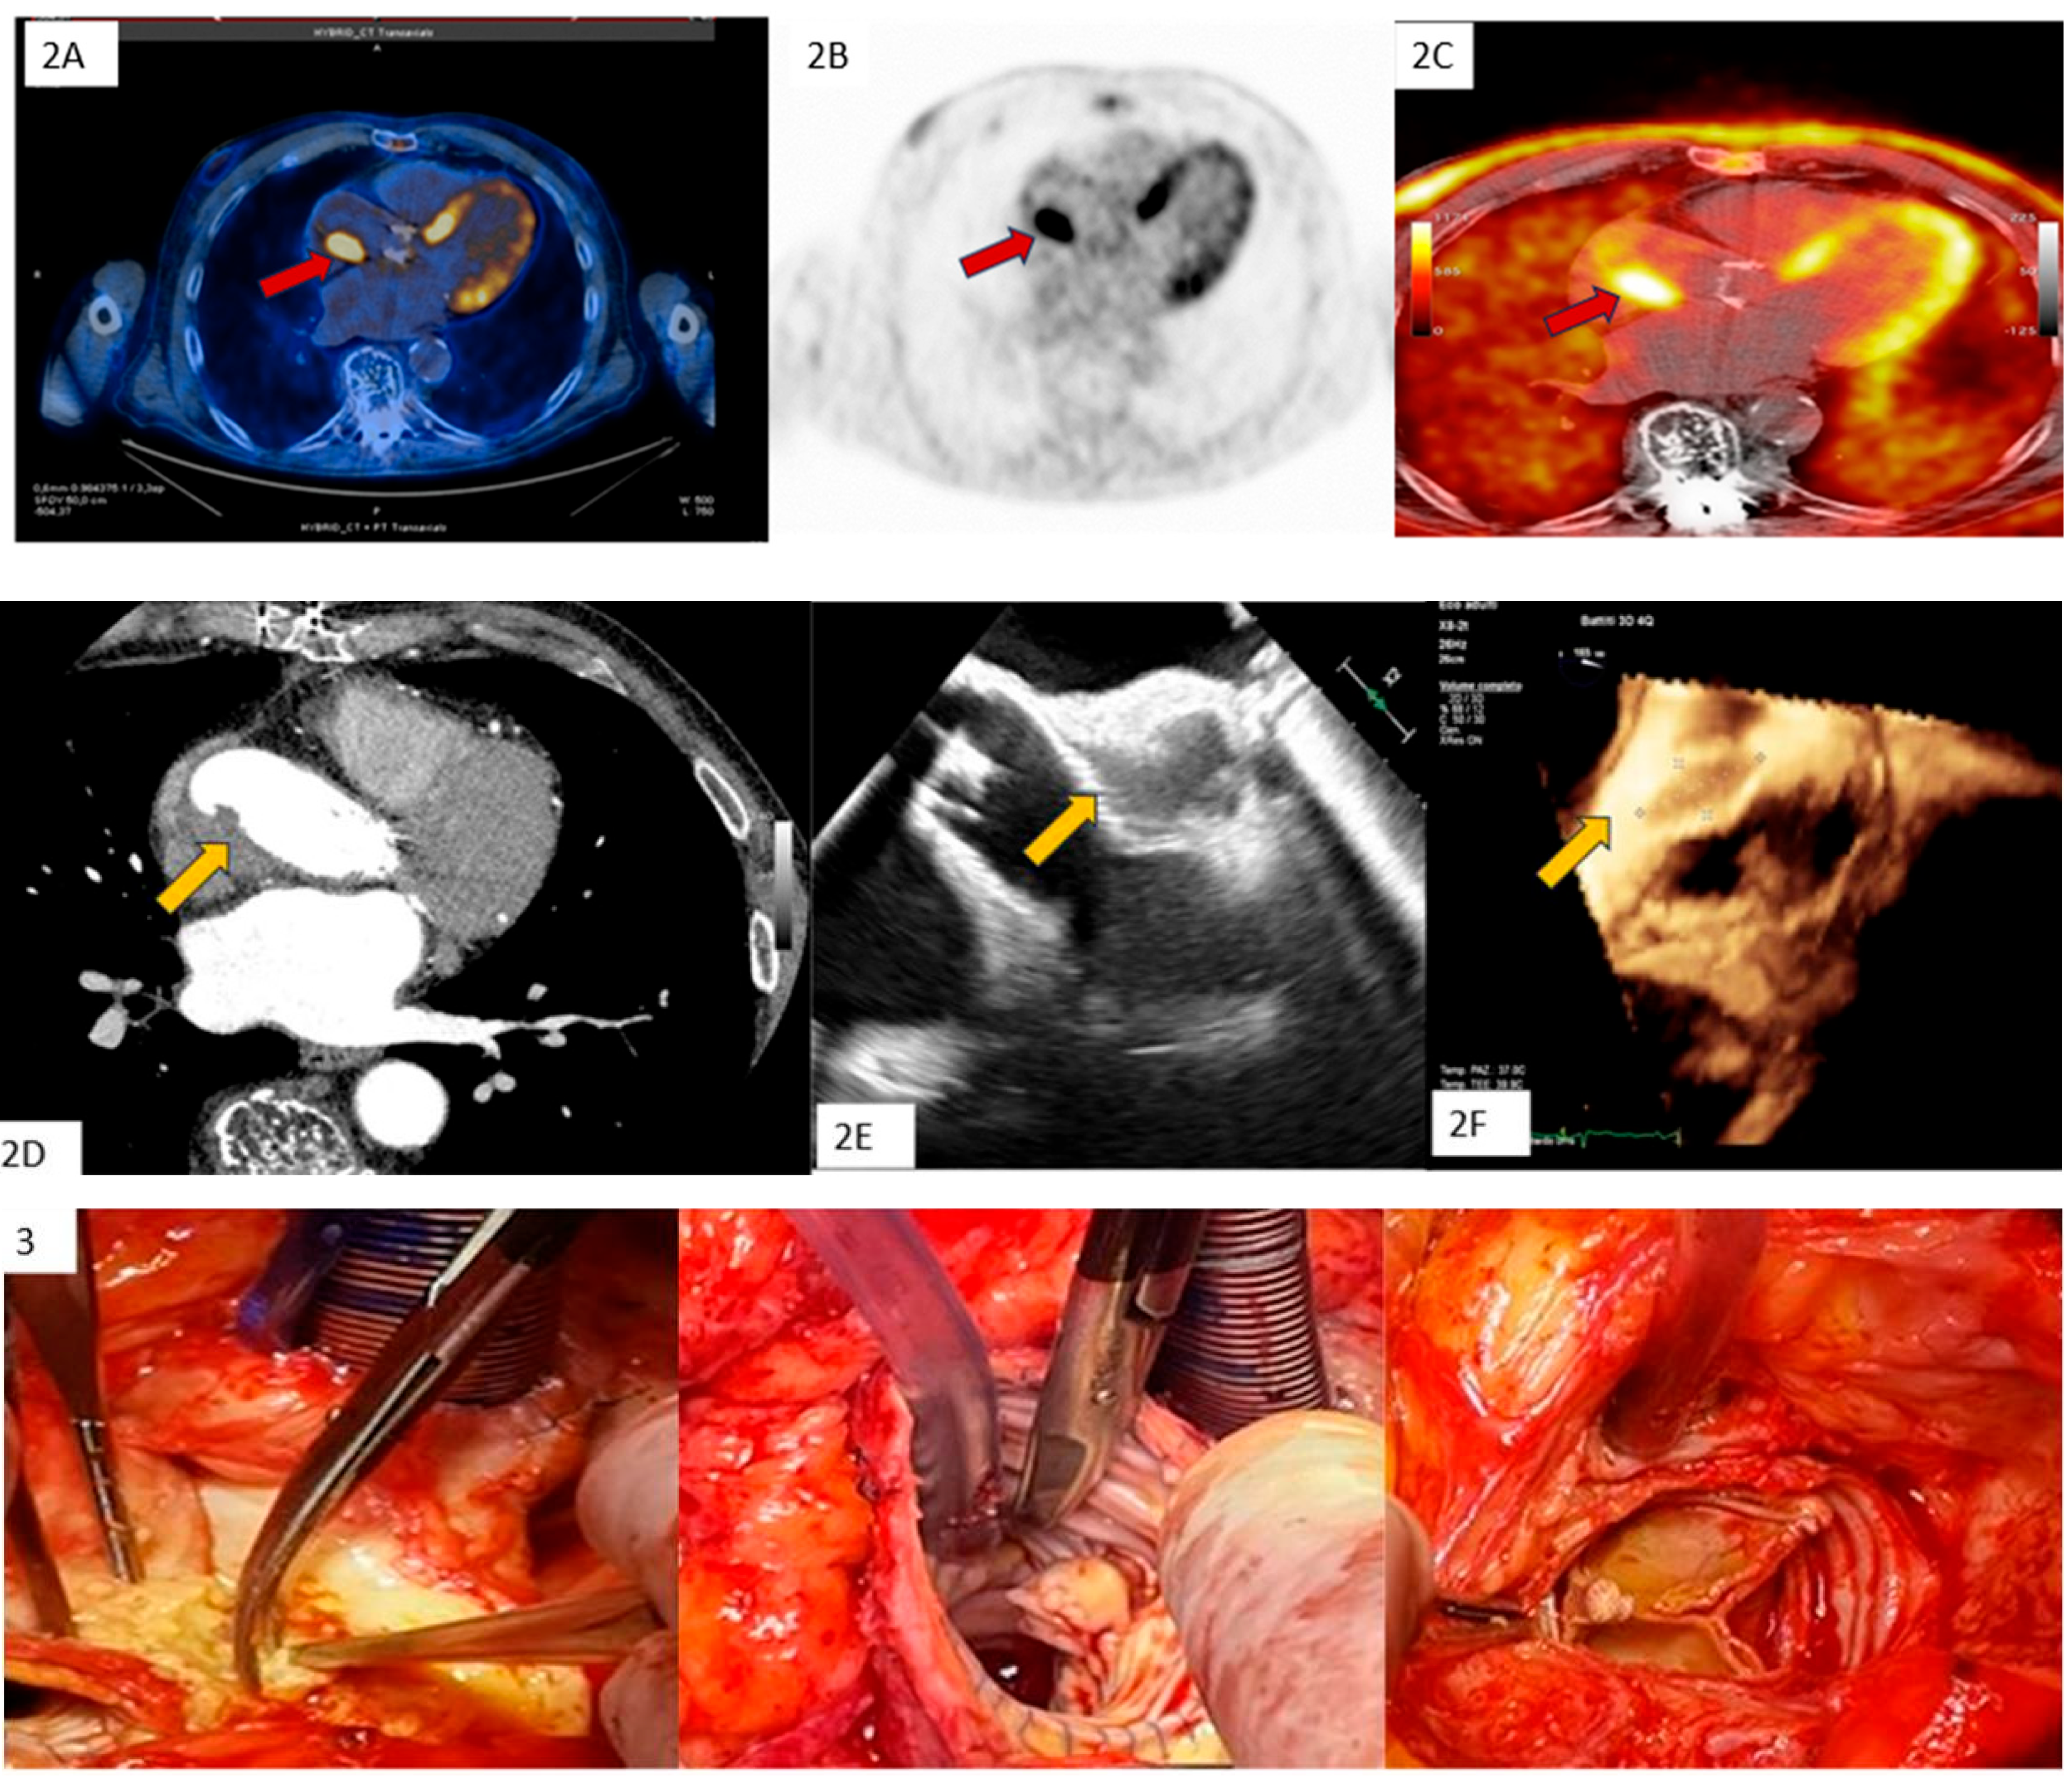

Clinical Case 2. Unexpected endocarditis at opprtunistic echocardiography follow-up. A 60-year-old woman was observed at our heart valve clinic for a scheduled 3-month survey following surgical mitral valve repair of prolapse-related mitral regurgitation. The patient was asymptomatic under medical therapy, including a beta-blocking agent and routine early anticoagulation with dicumarol. Clinical examination was normal. Transthoracic echocardiography showed a small iso-echogenic mass on the atrial side of the posterior mitral leaflet. The subsequent transesophageal echocardiography (1 = 2D-TEE, 2 = 3D-TEE), showed a large iso-echogenic mass with an annular infiltrative appearance suggesting active valve vegetation. Blood cultures and phlogistic indices were normal. A PET examination (3 = PET) showed moderate mitral ring uptake, coherent with the recent surgical procedure. Due to the unexpected findings suggesting IE without clinical and microbiological associated criteria, TEE was re-evaluated following seven-day treatment with iv Heparin and empirical antibiotic therapy (Vancomicin, Gentamicin, Rifampicin). Owing to the persistence of mitral valve mass at high embolic risk, the patient underwent surgery. Surgical inspection (4 = surgical specimen) and histological examination confirmed IE diagnosis with a microbiological tissue culture for Enterobacter Cloacae. Following mitral valve replacement the clinical course was favorable with 1-month focused antibiotic therapy, without IE recurrence at long-term follow-up. This case underscores the importance of a careful and systematic survey following cardiac surgery to exclude silent unexpected endocarditis, especially during the first year after heart valve surgery.

![]() |